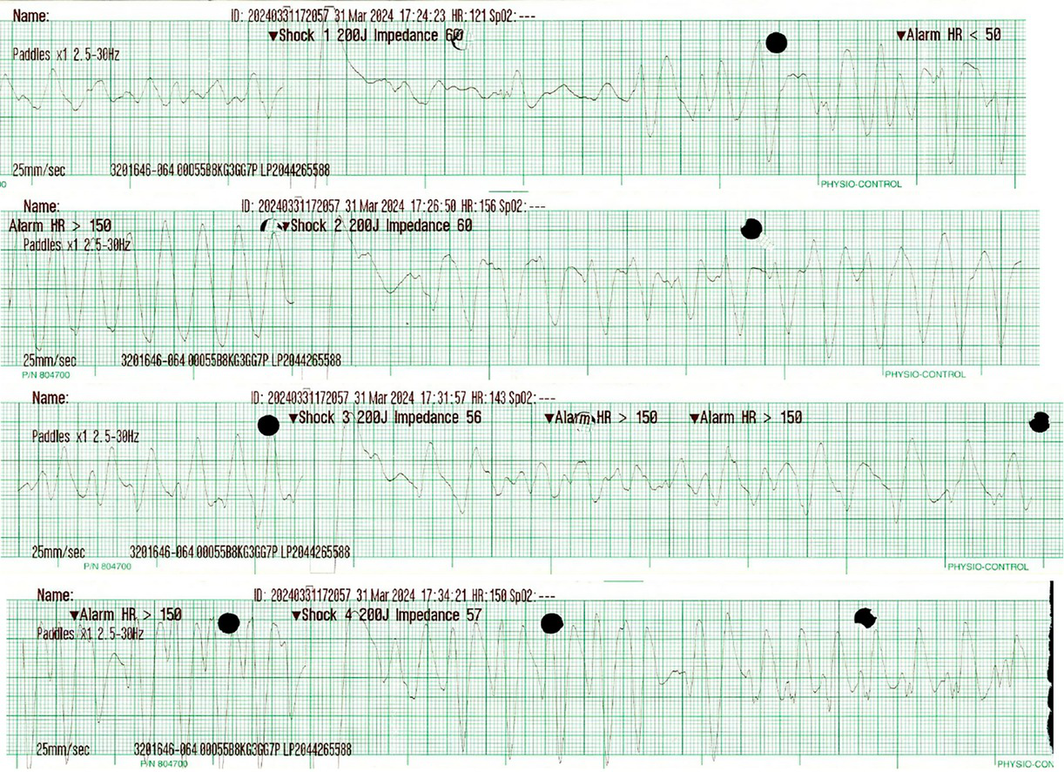

The patient underwent 19 minutes of cardiopulmonary resuscitation (CPR), including four defibrillator shocks of 200 J for ventricular fibrillation (Box 1) and pulseless ventricular tachycardia before return of spontaneous circulation (RoSC) of a broad complex tachycardia with palpable pulse (Box 2).